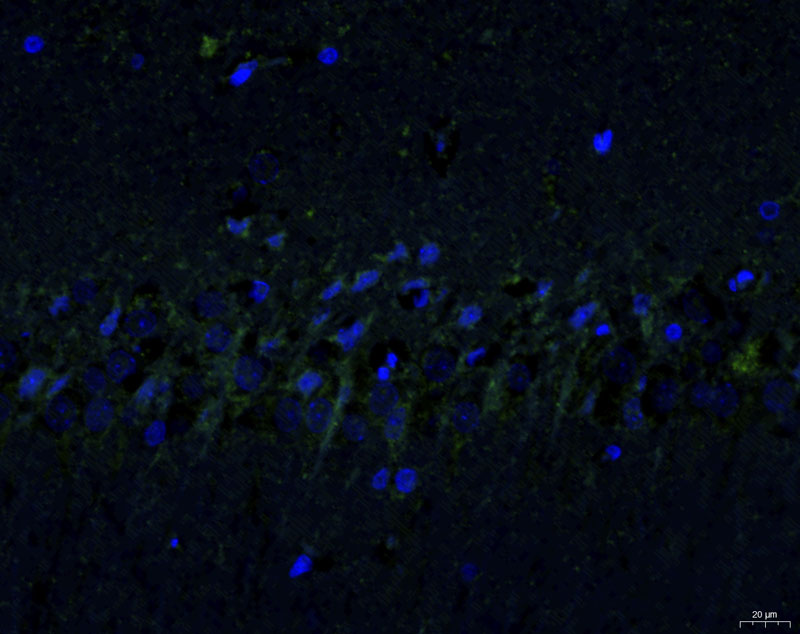

免疫熒光【組織染色 免疫組化】